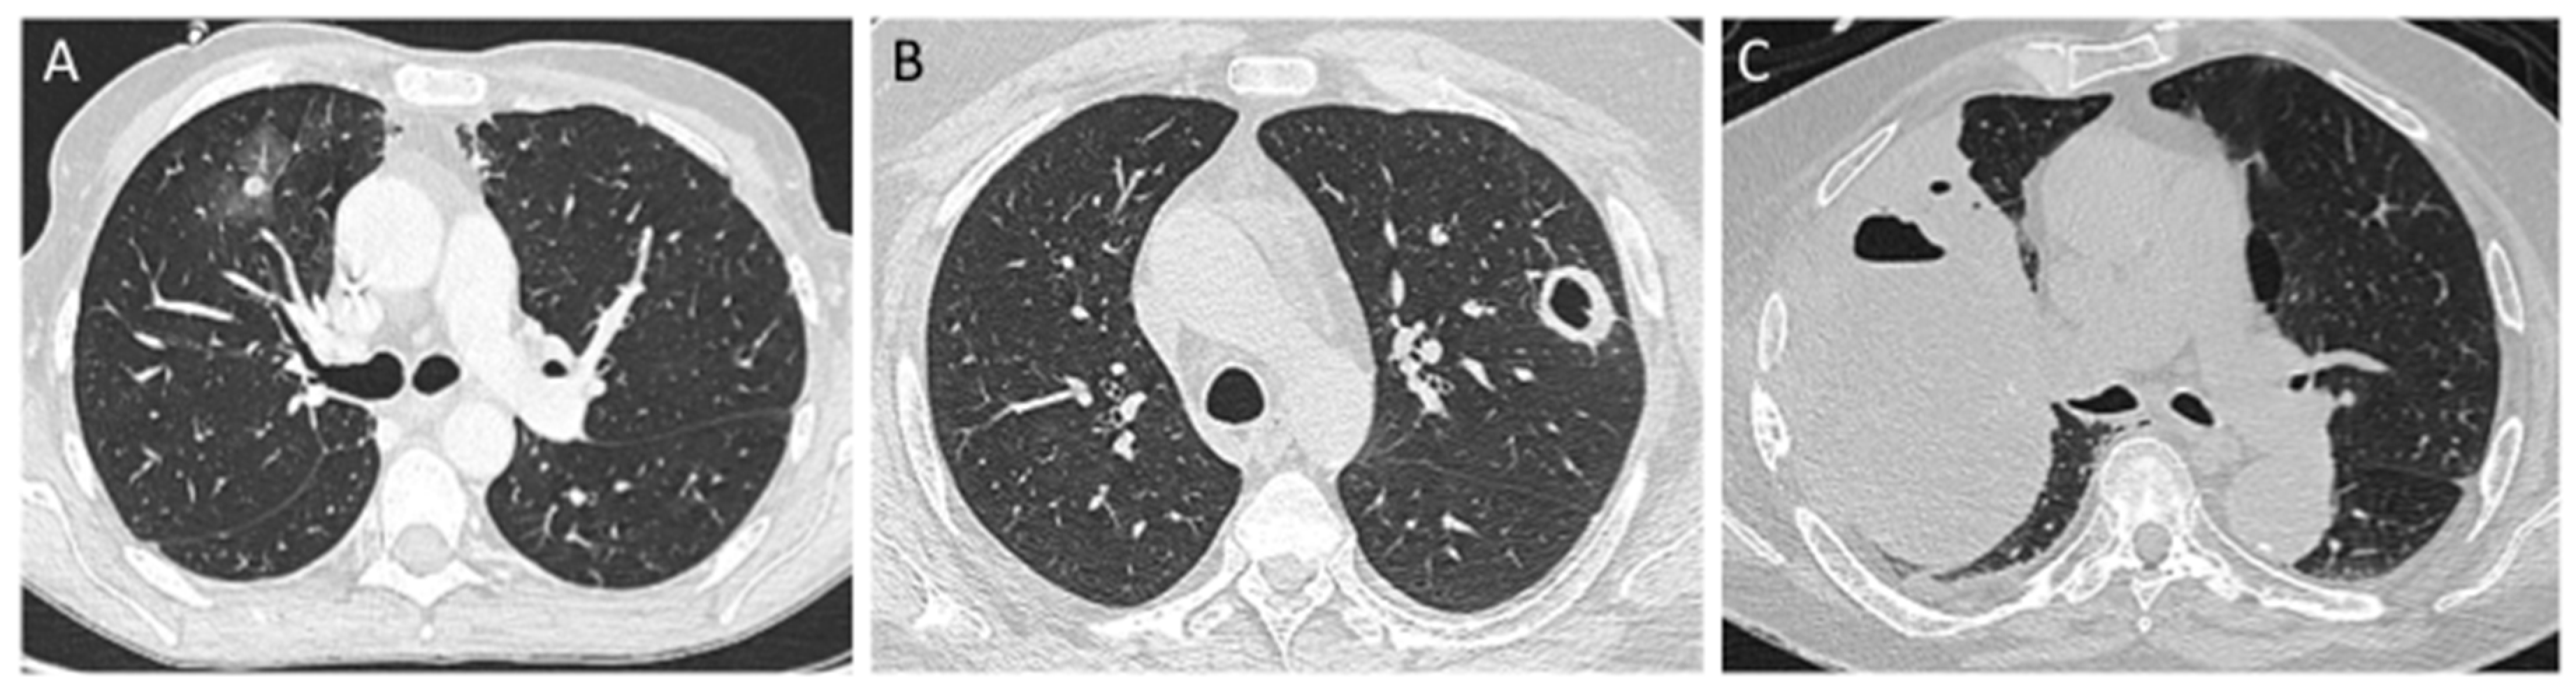

3. Pulmonary Mucormycosis (PM)